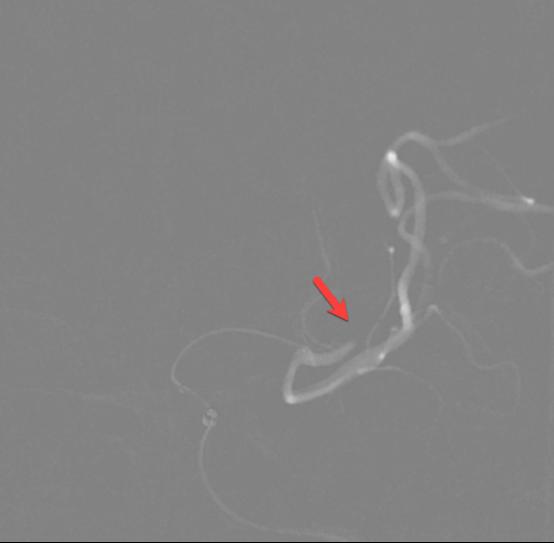

58岁的李大哥1周前有晕倒病史,但是没有到医院系统的治疗。发病前5个小时被人发现说不出话,右侧肢体不能活动。在我院神经内科急诊完善头颈部动脉CTA+CTP提示左侧大脑半球大片缺血带(图1)。是怎么回事呢?细心的血管介入科医生经过认真的分析图像,发现李大哥左侧颈内动脉存在的一个非常局限性的闭塞(图2、3),由于该段血管迂曲的走行在颅骨内不宜被发觉。得益于我院卒中团队的丰富经验,患者很快经绿色通道送至导管室准备手术。

在转运的过程中,患者症状持续加重,完全失语、右侧肢体全瘫同时意识逐渐模糊。糟糕,一定是左侧颈内动脉闭塞后血流缓慢继发颅内血栓形成。时间就是大脑,为挽救李大哥的生命,民航总医院卒中团队高效运作起来,神经内科、血管介入科、麻醉科迅速完成了患者的转运、麻醉及造影。如术前所料,患者左侧颈内动脉C6段闭塞(图4、5),左侧大脑中动脉M2段血栓形成(图6)。一个一个环环相扣的动作,一个一个精细无间的配合,血管介入科团熟练的完成了取栓支架就位(图7)、取出大脑中动脉血栓、植入颈内动脉支架(图8)等一系列操作,成功的开通了血管,恢复了颅内的血流(图9、10)。

图1

图2

图3